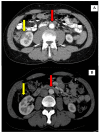

Conclusions: Lung and/or cardiovascular involvement were diagnosed in 15 (15.3%) patients in our historical cohort of patients with AIP type 1. Most of the lung involvement was presented in the form of nodular lesions in the lungs, non-specific infiltrates, "ground-glass" appearance with pleura thickening, and effusion. Aortic involvement was a major form of vascular involvement in patients with AIP, as in previous published studies on patients with IgG4-RD.